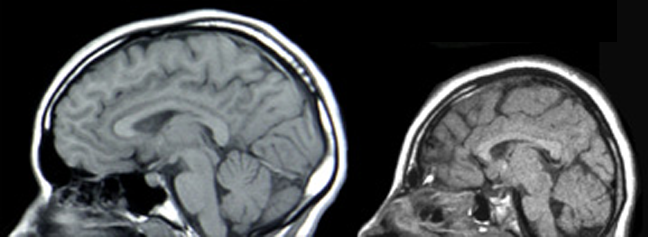

A normal brain and a microcephalic brain (source: wikipedia)

On this sunny, snowy, cold morning I am remembering a child that was born in (if I remember right) October of 1992. Her mother had been quite ill throughout the pregnancy, and the little girl was extremely premature. She suffered from numerous medical problems, nearly all of which were likely to be fatal. And yet that December, after a long stay in The Mayo Clinic’s Neonatal ICU and numerous surgeries, she was finally able to go home.

Although many of her immediate health challenges had been overcome, her microcephalic brain was not so easily repaired: it was 1/3rd the volume it should have been. Her parents were told she would be a “vegetable for the rest of her life.”